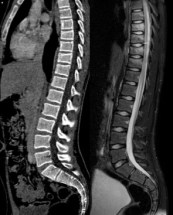

les fractures cunéiformes antérieures

elles sont souvent multiples en raison de l’élasticité rachidienne. L’IRM est utile pour connaitre l’extension réelle des lésions traumatiques (figure ci-contre).